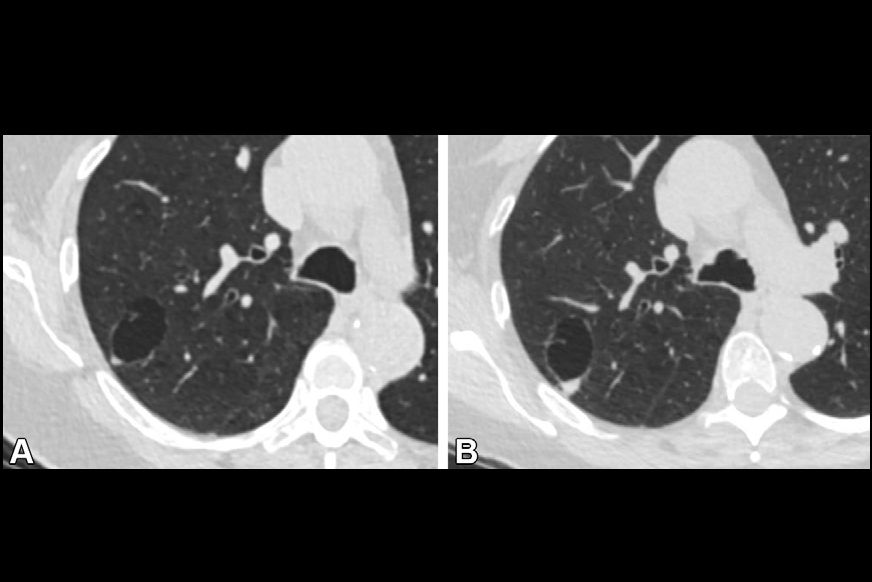

A new study published today in Radiology is bolstering the argument for CT lung screening by determining that cancers detected on screening scans are very similar to the ones diagnosed outside of the screening setting.

CT lung screening has received renewed interest following the publication of results in 2010 indicating that screening could reduce mortality by more than 20% in a population of current and former smokers. But one argument being used against the implementation of broad-based CT screening is that it might detect slow-growing cancers that might never pose a threat to individuals; working up these cancers would be expensive and could cause patient morbidity, the argument goes.

Today's results may allay those concerns, according to an article in our CT Digital Community. In the study, a group led by Dr. Claudia Henschke analyzed the characteristics and progression of screen-detected cancers and compared them to lesions found under normal clinical conditions. The result: there wasn't much difference between the two.